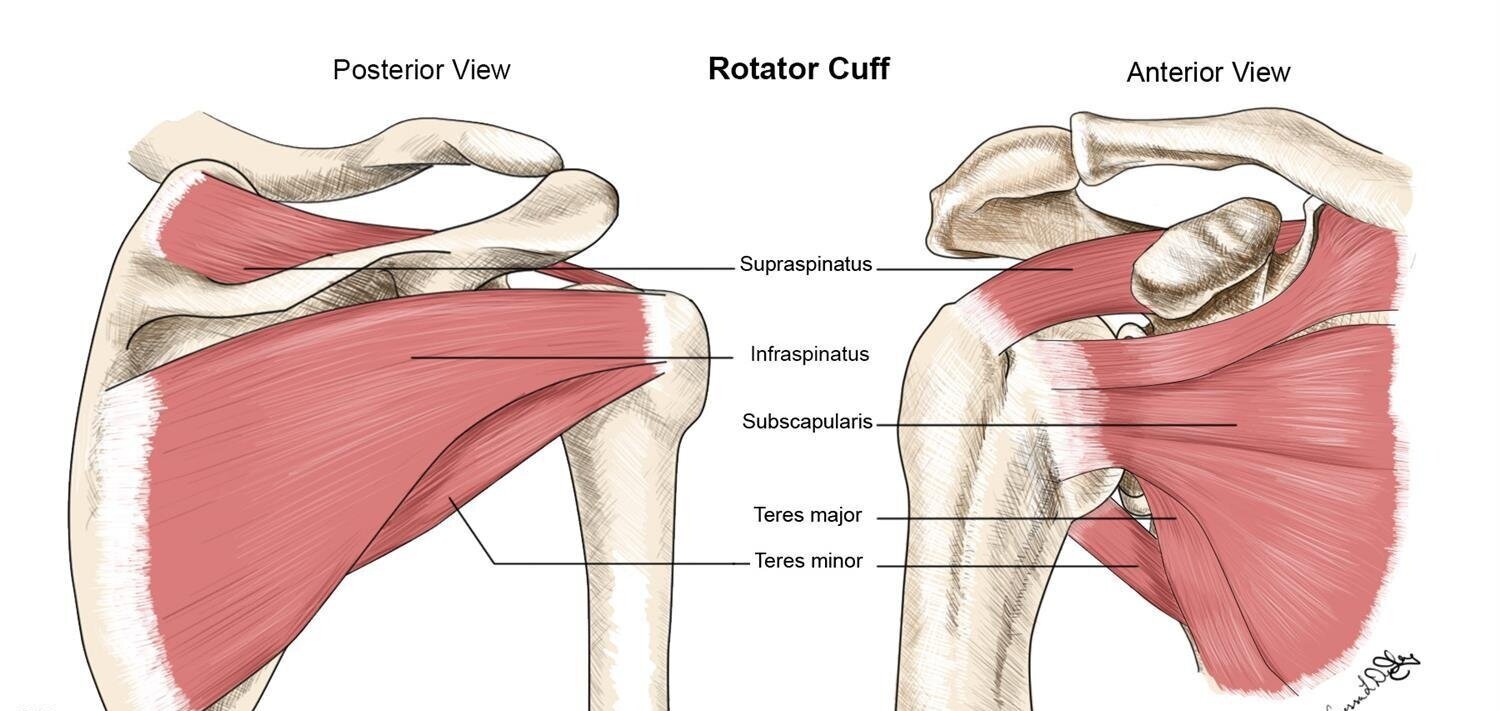

What is the rotator cuff?

group of muscles that stabilize the shoulder joint by pulling the humeral head into the glenoid fossa

What 4 muscles make up the rotator cuff?

supraspinatus, infraspinatus, subscapularis, and teres minor

Explain the location and function of the supraspinatus muscle

originates on the upper border of the posterior scapula

allows for abduction

Explain the location and function of the subscapularis muscle

originates on the anterior surface of the scapula

allows for internal rotation

Explain the location and function of the infraspinatus muscle

originates on the posterior inferior aspect of the scapula

allows for external rotation

Explain the location and function of the teres minor muscle

originates on the posterior lateral scapular border

allows for external rotation

Label the muscles of the rotator cuff